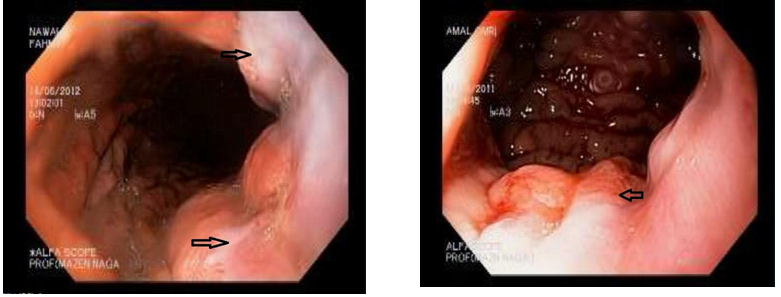

Junctional varices may be easily missed during endoscopic examination as they are usually multiple and are frequently mistaken for gastric folds. This may explain the significantly higher incidence of rebleeding from junctional varices (38.6%) compared to fundal varices (12.4%) despite injecting both by glue (Figures 1-3).

Junctional varices has a significantly high rate of rebleeding as they may be easily missed during endoscopic examination as they are usually multiple and are frequently mistaken for gastric folds especially if they are not actively bleeding. An important observation in our study that we found that varices that occur distal to gastroesophageal junction (classified as GOV1) are not in communication with esophageal varices we reached this conclusion by the observation that in the post injection X ray films, Histoacryl injection of the junctional varices (GOV1) below the Z line showed that the Histoacryl didn’t go up above the Z line, while injection of the esophageal varix above the Z line fills the whole column of the varix (Figure 1).